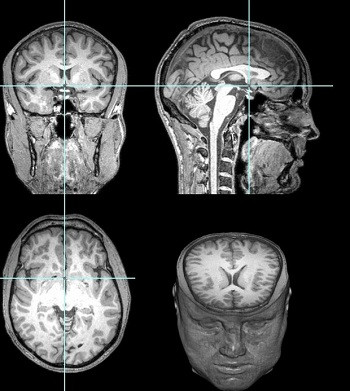

Các vùng trong não Gareyev liên kết tốt hơn so với người bình thường. Ảnh: Jesse Rissman.

Bước tiếp theo đó là quét não. Rissman quan sát sự kết nối giữa các vùng trong não bộ của Gareyev. Kết quả cho thấy, sự liên kết giữa các vùng trong não Gareyev tốt hơn mức trung bình, tạo thành mạng lưới kiểm soát liên kết thùy trán với thùy đỉnh. Trong số 63 người tham gia quét não cùng anh, chỉ có một, hai người đạt kết quả cao hơn.

Kết quả quét não cũng chỉ ra, màng lưới thị giác của Gareyev kết nối với các vùng khác trong não tốt hơn người bình thường. Điều này chứng tỏ, vùng xử lý hình ảnh thị giác, ví dụ như bàn cờ, trong não Gareyev có thể liên kết chặt chẽ hơn với các vùng khác của não, nhờ vậy hoạt động mạnh hơn thông thường. Đây có thể là manh mối nhằm giải đáp khả năng đặc biệt của Gareyev.